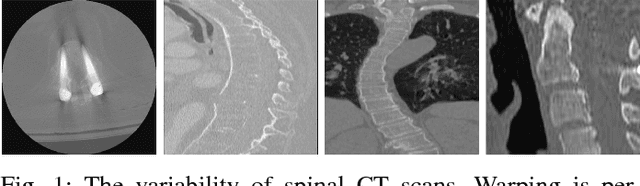

Abstract:Automatic vertebrae identification and localization from arbitrary CT images is challenging. Vertebrae usually share similar morphological appearance. Because of pathology and the arbitrary field-of-view of CT scans, one can hardly rely on the existence of some anchor vertebrae or parametric methods to model the appearance and shape. To solve the problem, we argue that one should make use of the short-range contextual information, such as the presence of some nearby organs (if any), to roughly estimate the target vertebrae; due to the unique anatomic structure of the spine column, vertebrae have fixed sequential order which provides the important long-range contextual information to further calibrate the results. We propose a robust and efficient vertebrae identification and localization system that can inherently learn to incorporate both the short-range and long-range contextual information in a supervised manner. To this end, we develop a multi-task 3D fully convolutional neural network (3D FCN) to effectively extract the short-range contextual information around the target vertebrae. For the long-range contextual information, we propose a multi-task bidirectional recurrent neural network (Bi-RNN) to encode the spatial and contextual information among the vertebrae of the visible spine column. We demonstrate the effectiveness of the proposed approach on a challenging dataset and the experimental results show that our approach outperforms the state-of-the-art methods by a significant margin.